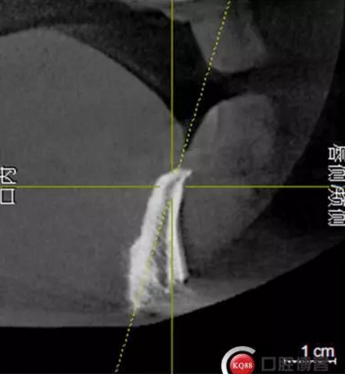

檢查:上頜無(wú)牙頜假牙穩(wěn)定性尚可,下頜3435364243殘根;33殘冠1-2度松動(dòng),其他牙齒缺失;CBCT檢查:下頜牙槽骨前牙區(qū)骨高度足,后牙區(qū)骨高度最低為8mm,骨寬度足。

1)術(shù)前檢查,拍攝臨床照片及CBCT檢查,制取活動(dòng)義齒參考模型,指導(dǎo)后期最終修復(fù)的牙齒排列

2)術(shù)前準(zhǔn)備及手術(shù)過(guò)程,測(cè)量血壓及血糖,簽種植知情同意書(shū);嚴(yán)格遵循無(wú)菌操作,局麻下采用微創(chuàng)技術(shù)于323436分別植入osstem4.0X10,4.0X10,4.5X7; 434446分別植入osstem4.0X1O,4.0X10,4.5X7.初期穩(wěn)定性均達(dá)到了35N.CM以上;嚴(yán)密縫合,止血,種植體位點(diǎn)和方向與設(shè)計(jì)一致。